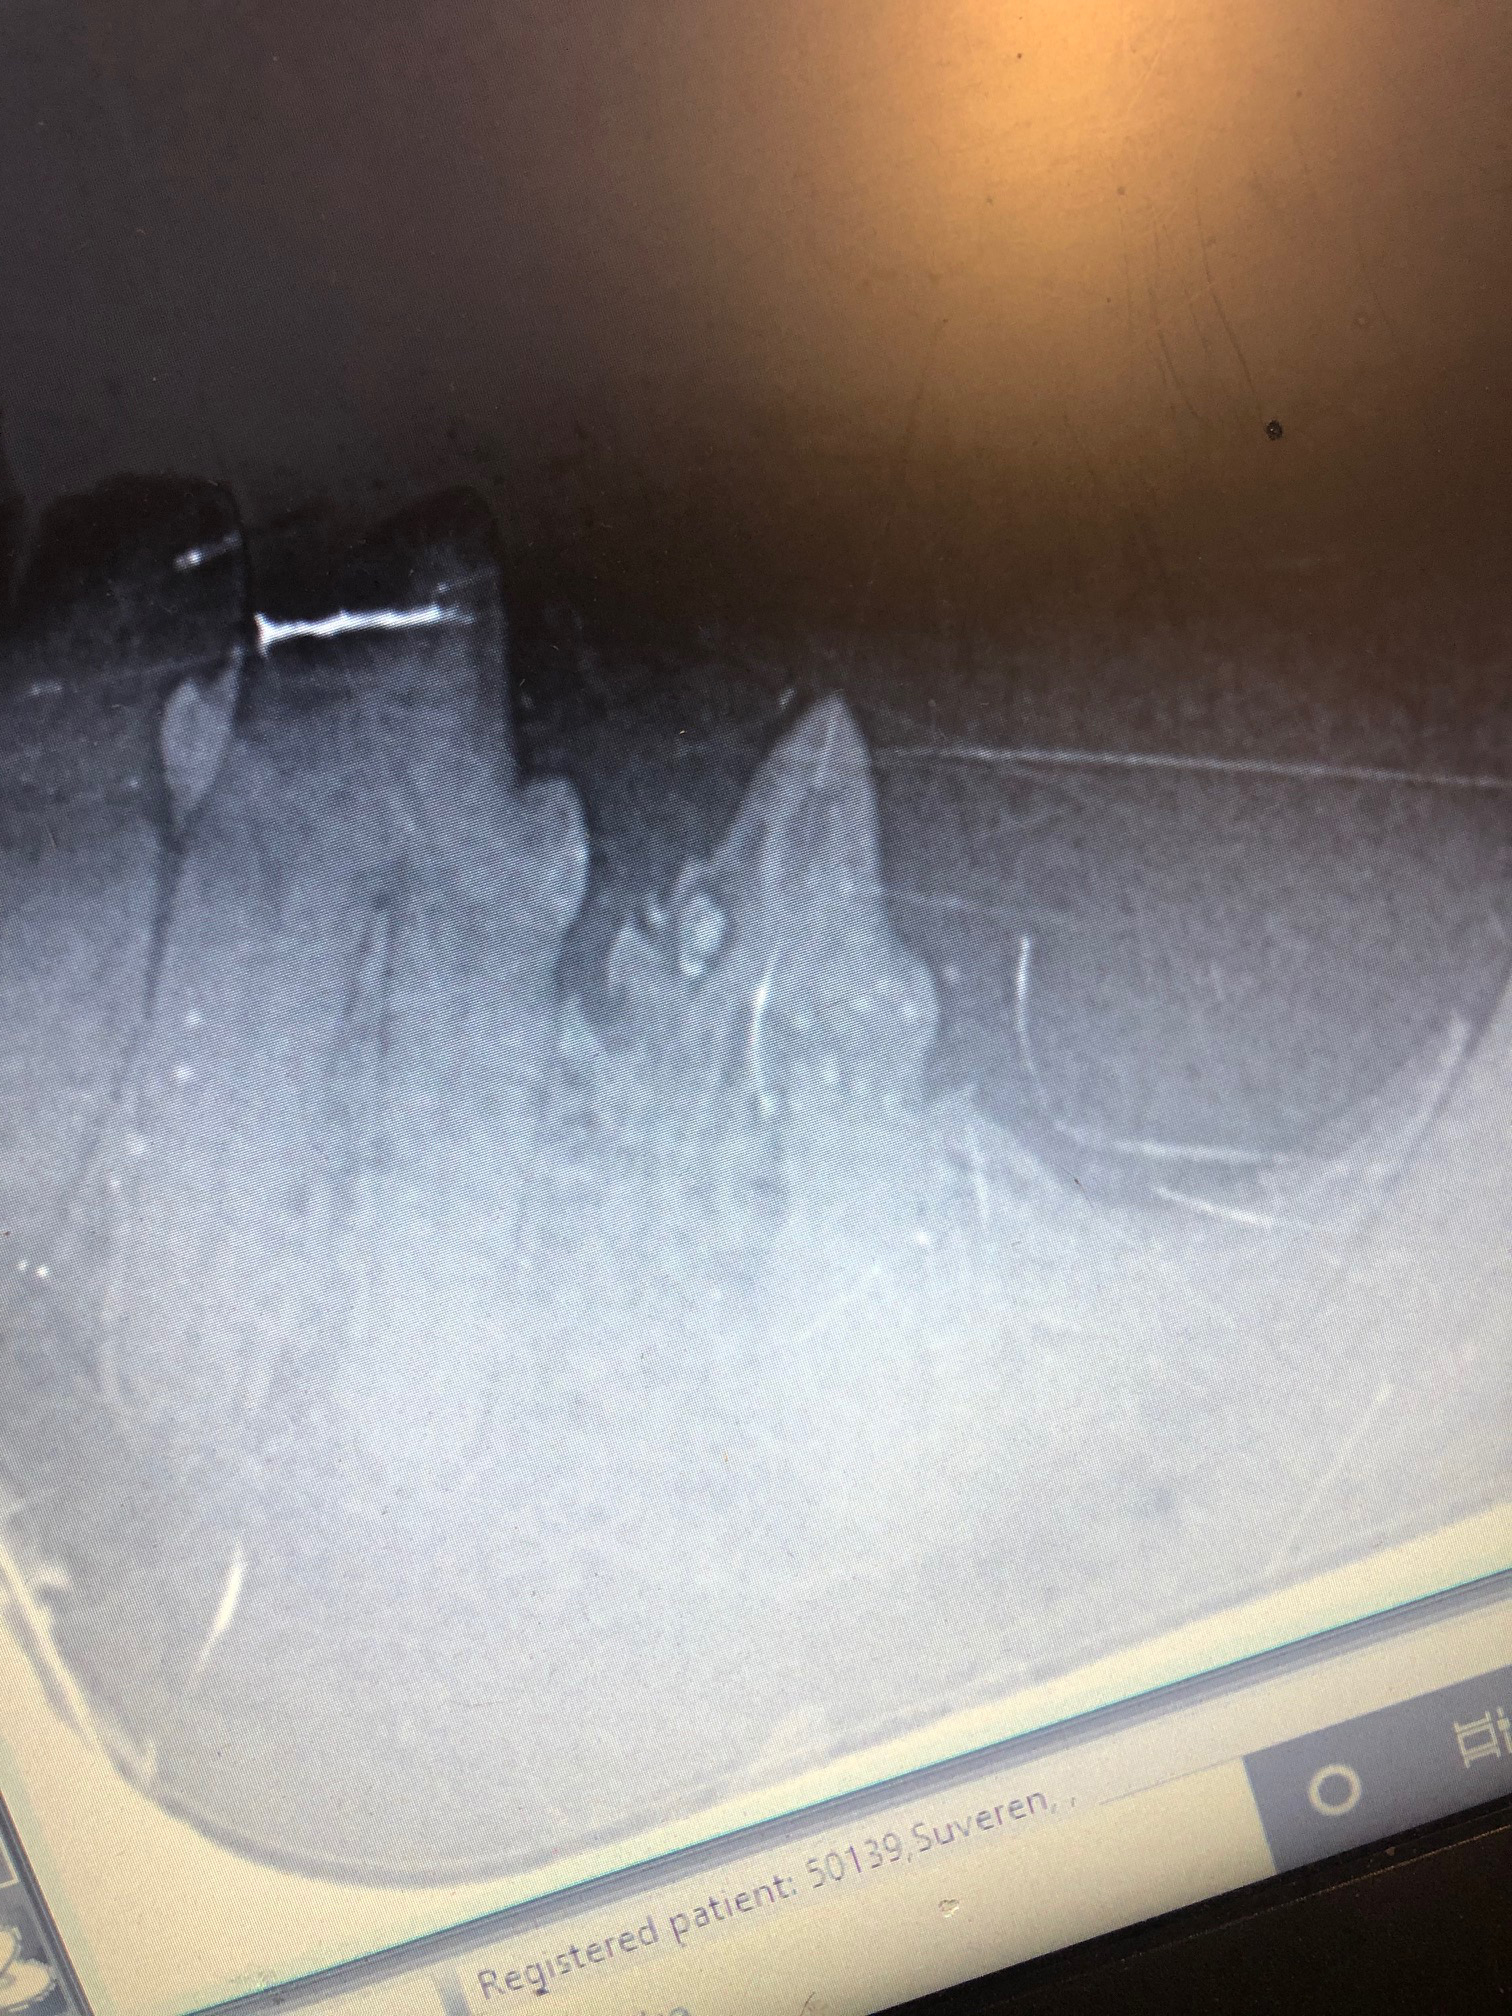

Roxi huskatt kom inn på klinikken fordi eierne hennes hadde oppdaget en liten hudirritasjon på den ene siden av munnen som ikke ville gro/bedre seg. Lite visste de at Roxi gikk med smerter i munnen grunnet en ganske vanlig tannsykdom som rammer katter som vi kaller TR - "tooth resorption" eller tann nedbrytning. Typisk rammer denne sykdommen de første kinntennene i underkjeven (se bilde under).

Ved undersøkelse av munnhulen oppdaget veterinæren forandringer på en tann - det var hakk i tanna og rødt tannkjøtt og dette ble undersøkt videre i narkose med tannrøntgen som viste tydelig at tanna var full av hull og roten brutt ned. Sykdommen bryter nemlig ned tennene - og det er ikke alltid man ser noe på selve tannen heller, derfor er tannrøntgen et viktig verktøy for å få oversikt over sykdommen.